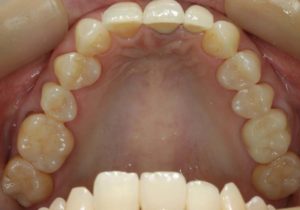

治療お疲れ様でした。たくさん銀歯が入っていたのですが、最後には真っ白になりましたね。銀歯をやり直す材料にはセラミックとプラスティックがあるのですが、基本的にできるだけプラスティックで治すようにしています。この患者さんも、可能な限りプラスティックで治し、どうしても無理なところだけセラミックにしました。そのため歯を削る量が少ないことに加え、費用もかなり抑えることができます。たくさん治しましたが、全部セラミックで治さなければならないとなっていたら、もっともっと時間も費用もかかっていたかもしれません。当院では、初診時に治療方針や期間や費用などを1時間ほどかけて詳しく説明していますので、患者さんには治療内容について十分納得していただいていると考えています。「親身になって治療してくれる」とおっしゃっていただいたことは、そういったところを評価して頂いたのではいかと思っております。

- 術前

- 術後